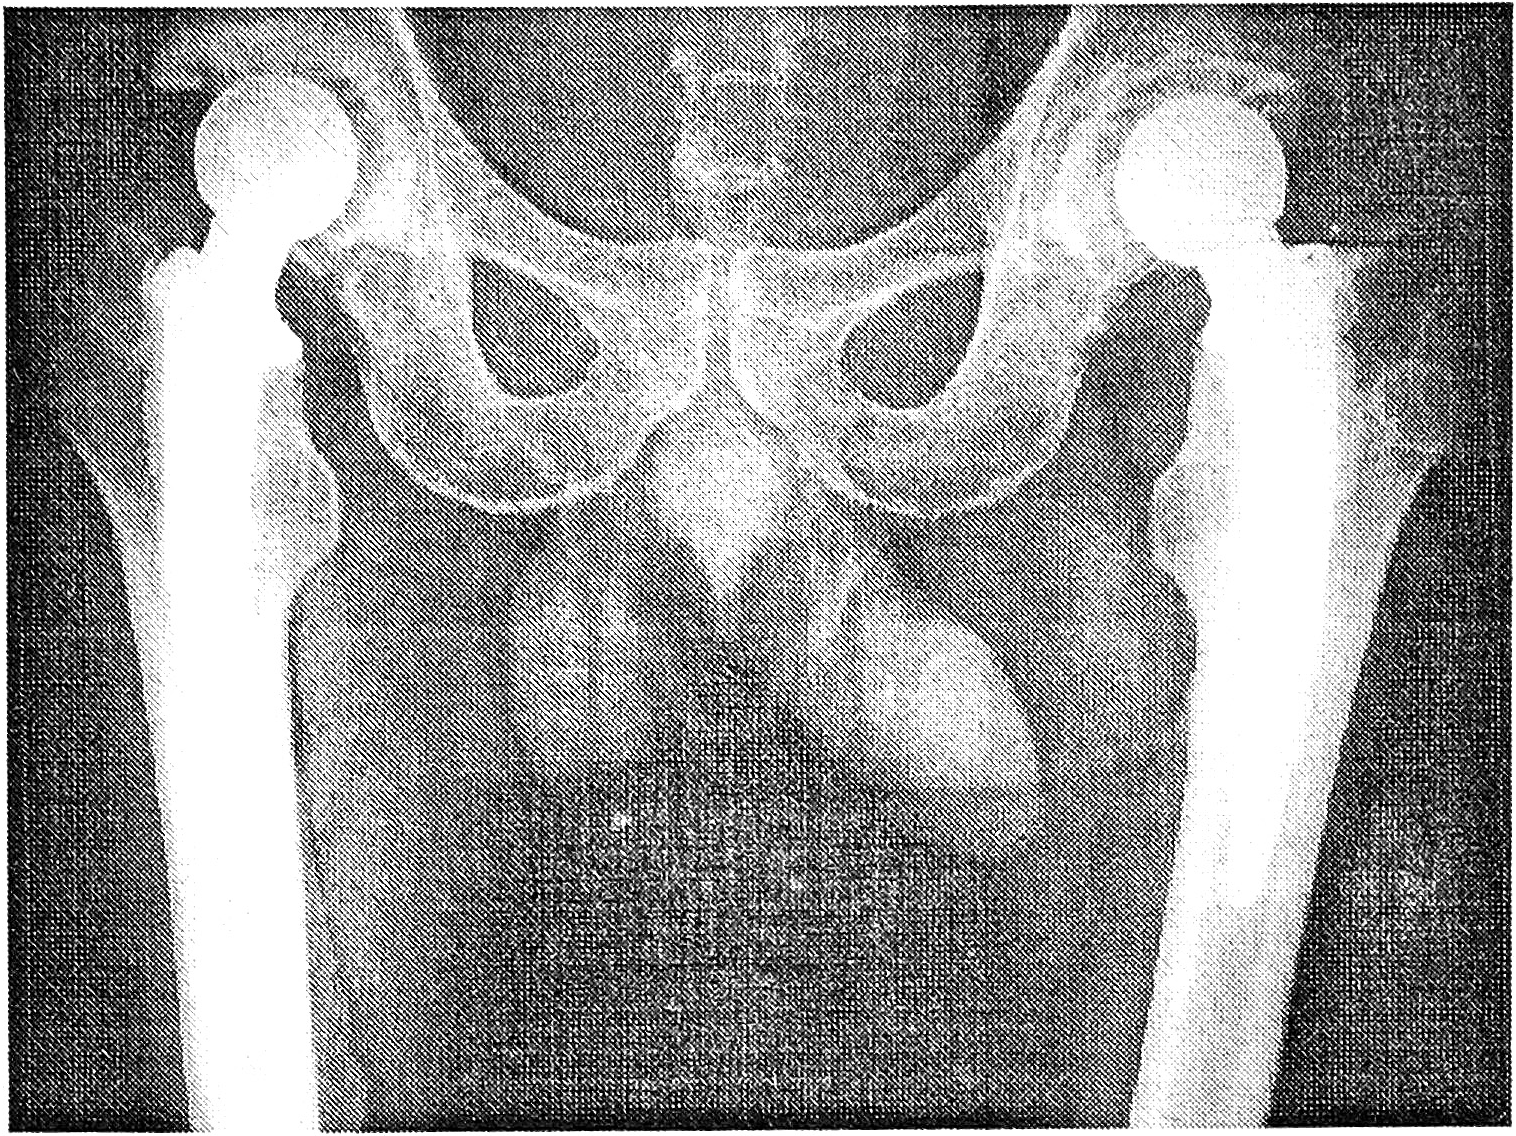

Изучение ближайших и отдаленных (от 6 мес до 18 лет) результатов тотального и цервикокапитального эндопротезирования, в основном имплантатами фирмы «Beznoska» (Чехия), показало, что все пациенты избавились от мучительных болей в суставах, почти в полном объеме восстановились движения в них и нагрузка на конечности; пациенты, у которых не возникло осложнений, за редким исключением, не пользуются тростью. Положительные исходы констатированы у 93% больных (рис. 2).

Рис. 2. Рентгенограммы больного после двустороннего тотального эндопротезирования тазобедренного сустава.